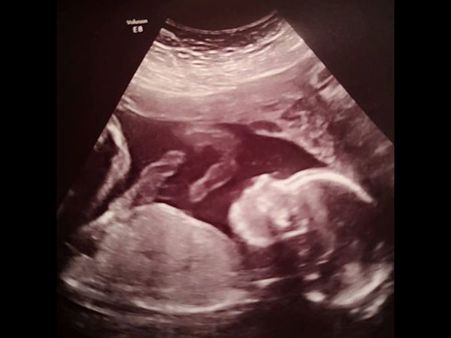

The 26-year-old woman and her partner were given the option to terminate the pregnancy after the tests revealed that the unborn baby had spina bifida. The medics discovered this in a routine 20-week scan where they realised that the unborn baby's head was not the right measurement.

The doctors offered the couple a new option called as foetal surgery where they would fix the unborn child's condition even before she is born. The surgery involved removing the unborn baby from the mother's womb and repairing the spinal cord of the child, so that the baby has greater chances of leading a normal life.